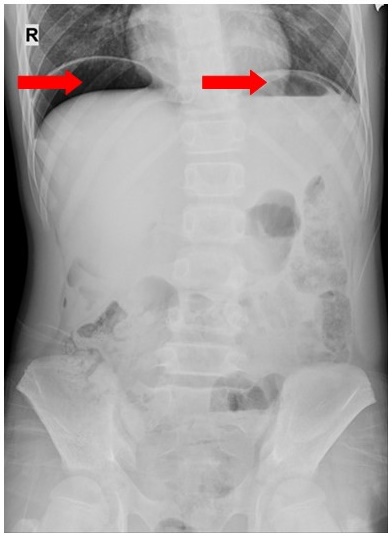

Hình ảnh liềm hơi dưới hoành hai bên trên phim chụp X-quang ổ bụng của bệnh nhi.

Ngày 1/11/2020 sau khi ăn tối, trẻ xuất hiện đau quặn bụng dữ dội quanh rốn, sau lan ra khắp bụng. Trẻ nôn 3 lần ra dịch tiêu hóa đã được đưa đến cấp cứu tại Trung tâm Y tế Thị xã Đông Triều, và được chuyển Bệnh viện Việt Nam – Thụy Điển Uông Bí tiếp tục điều trị. Qua thăm khám và kết quả chụp X-quang bụng với hình ảnh thủng tạng rỗng, các bác sĩ đã chỉ định phẫu thuật nội soi cấp cứu cho bệnh nhi.